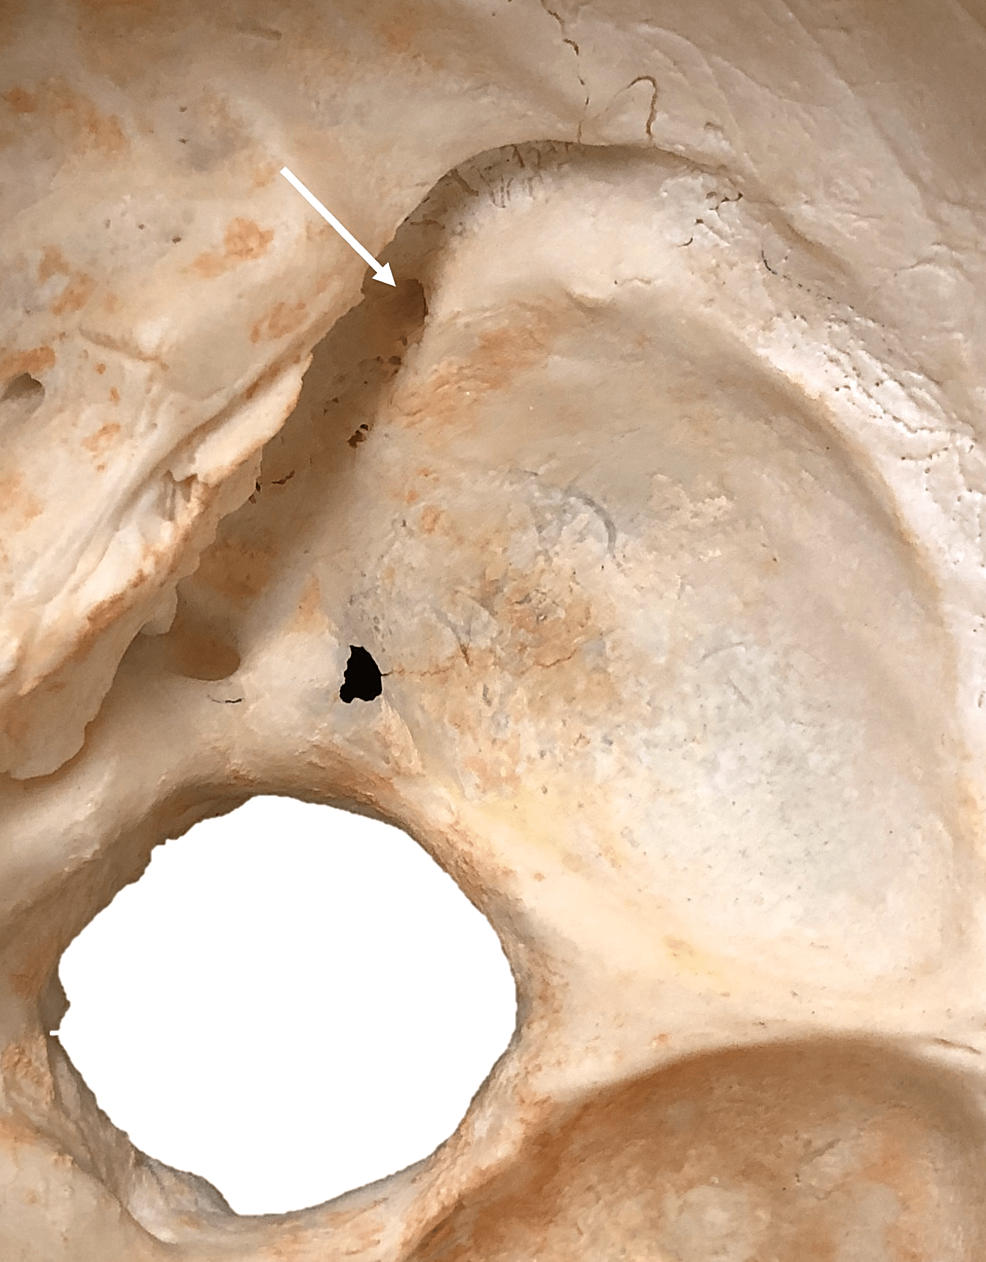

Cureus Granular Foveolae in the Groove of the Sigmoid Sinus An What Is The Groove For Sigmoid Sinus The main function of the sigmoid sinus is to conduct blood from the transverse sinus to the internal jugular vein. The sigmoid sinuses are paired, and they travel in the groove for the sigmoid sinus beneath the temporal bone, following a tortuous course to the. Along the way, the sigmoid sinus receives tributaries that collect blood from. The groove for. What Is The Groove For Sigmoid Sinus.

Cureus Granular Foveolae in the Groove of the Sigmoid Sinus An What Is The Groove For Sigmoid Sinus The sigmoid sinuses are paired, and they travel in the groove for the sigmoid sinus beneath the temporal bone, following a tortuous course to the. It crosses the jugular process of the occipital bone and turns forwards to end in the. The sigmoid sinus is a prominent venous structure in the brain’s dural venous sinus system, responsible for carrying blood. What Is The Groove For Sigmoid Sinus.

(PDF) Granular Foveolae in the Groove of the Sigmoid Sinus An What Is The Groove For Sigmoid Sinus Along the way, the sigmoid sinus receives tributaries that collect blood from. The groove for sigmoid sinus (a.k.a. It crosses the jugular process of the occipital bone and turns forwards to end in the. The sigmoid sinus (ss) is a paired venous sinus beginning as the continuation of the transverse sinus posteriorly, coursing downward. The sigmoid sinus is a prominent. What Is The Groove For Sigmoid Sinus.

Cureus Granular Foveolae in the Groove of the Sigmoid Sinus An What Is The Groove For Sigmoid Sinus The main function of the sigmoid sinus is to conduct blood from the transverse sinus to the internal jugular vein. Along the way, the sigmoid sinus receives tributaries that collect blood from. The sigmoid sinus (ss) is a paired venous sinus beginning as the continuation of the transverse sinus posteriorly, coursing downward. The sigmoid sinus is a prominent venous structure. What Is The Groove For Sigmoid Sinus.

(PDF) Granular Foveolae in the Groove of the Sigmoid Sinus Anatomical What Is The Groove For Sigmoid Sinus Sigmoid sulcus) is a continuation of the groove of the transverse sinus. The groove for sigmoid sinus (a.k.a. The sigmoid sinus is a prominent venous structure in the brain’s dural venous sinus system, responsible for carrying blood from the. The sigmoid sinus (ss) is a paired venous sinus beginning as the continuation of the transverse sinus posteriorly, coursing downward. The. What Is The Groove For Sigmoid Sinus.